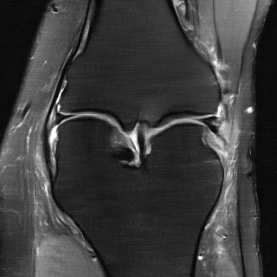

Deep Learning (DL) methods have shown promising results for solving ill-posed inverse problems such as MR image reconstruction from undersampled $k$-space data. However, these approaches currently have no guarantees for reconstruction quality and the reliability of such algorithms is only poorly understood. Adversarial attacks offer a valuable tool to understand possible failure modes and worst case performance of DL-based reconstruction algorithms. In this paper we describe adversarial attacks on multi-coil $k$-space measurements and evaluate them on the recently proposed E2E-VarNet and a simpler UNet-based model. In contrast to prior work, the attacks are targeted to specifically alter diagnostically relevant regions. Using two realistic attack models (adversarial $k$-space noise and adversarial rotations) we are able to show that current state-of-the-art DL-based reconstruction algorithms are indeed sensitive to such perturbations to a degree where relevant diagnostic information may be lost. Surprisingly, in our experiments the UNet and the more sophisticated E2E-VarNet were similarly sensitive to such attacks. Our findings add further to the evidence that caution must be exercised as DL-based methods move closer to clinical practice.